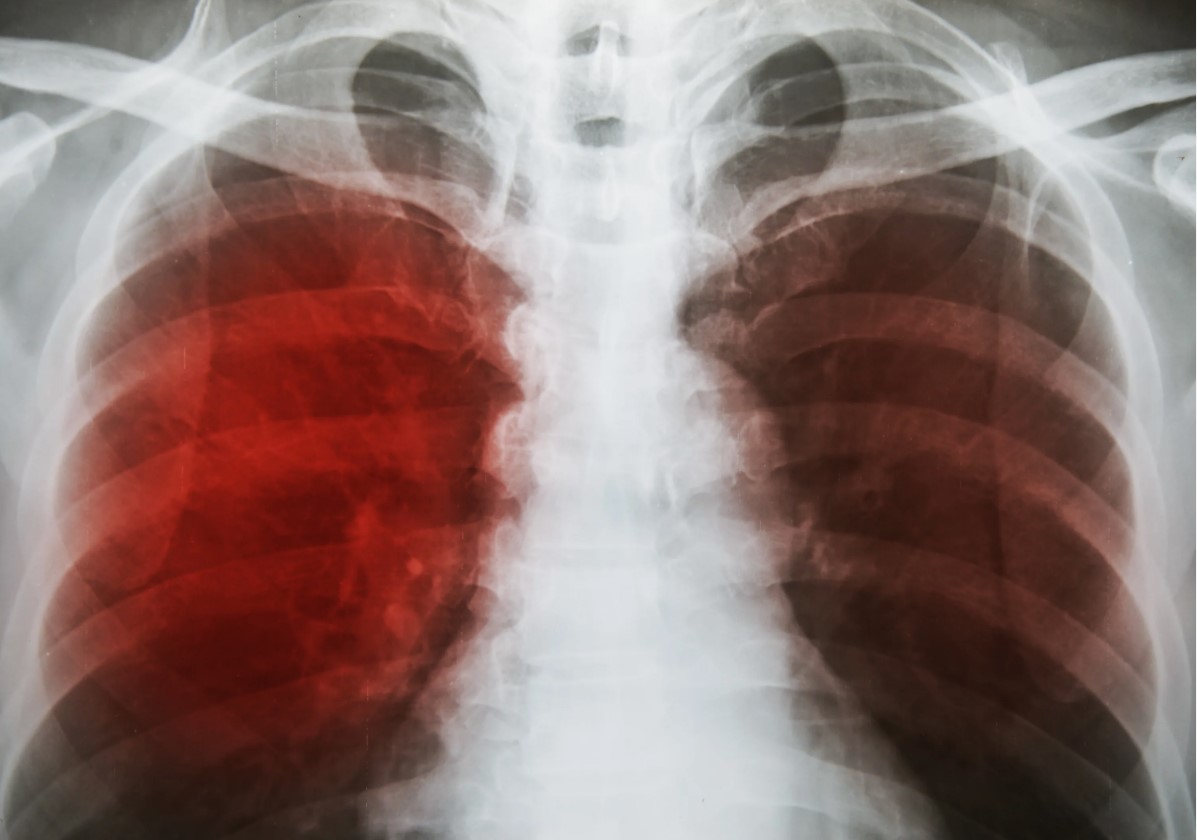

Туберкулез - серьёзное инфекционное заболевание, при котором в 80-90% случаев поражаются органы дыхания, однако очаги поражения могут находиться и в других органах и системах. Сейчас туберкулёз называют лидером по смертности среди инфекционных заболеваний.

Примерно 12-14 млн населения нашей планеты инфицированы одновременно ВИЧ и микобактериями туберкулёза. Такое сочетание особенно опасно, это фактически бомба для иммунитета. Но остановить развитие инфекции возможно даже в этом случае. Важно, чтобы в период профилактического лечения туберкулёза пациент получал антиретровирусную терапию (АРВТ), если по каким-то причинам он не принимал её ранее. Поскольку туберкулёз более опасен для ВИЧ-положительных людей, им в качестве профилактики рекомендуют делать флюорографию дважды в год, диаскинтест, при выраженном иммунодефиците компьютерная томография органов грудной клетки. Недавно были разработаны более аккуратные тесты на активную или латентную инфекцию - ELISPOT, определяющие лимфоциты, которые реагируют на фрагменты двух уникальных белков бактерии.